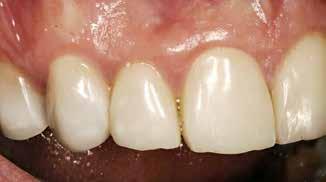

Postoperativ status

Fig. 4. Færdigrestaurerede tænder med komposit.

Fig. 4. Final restored teeth with composite.